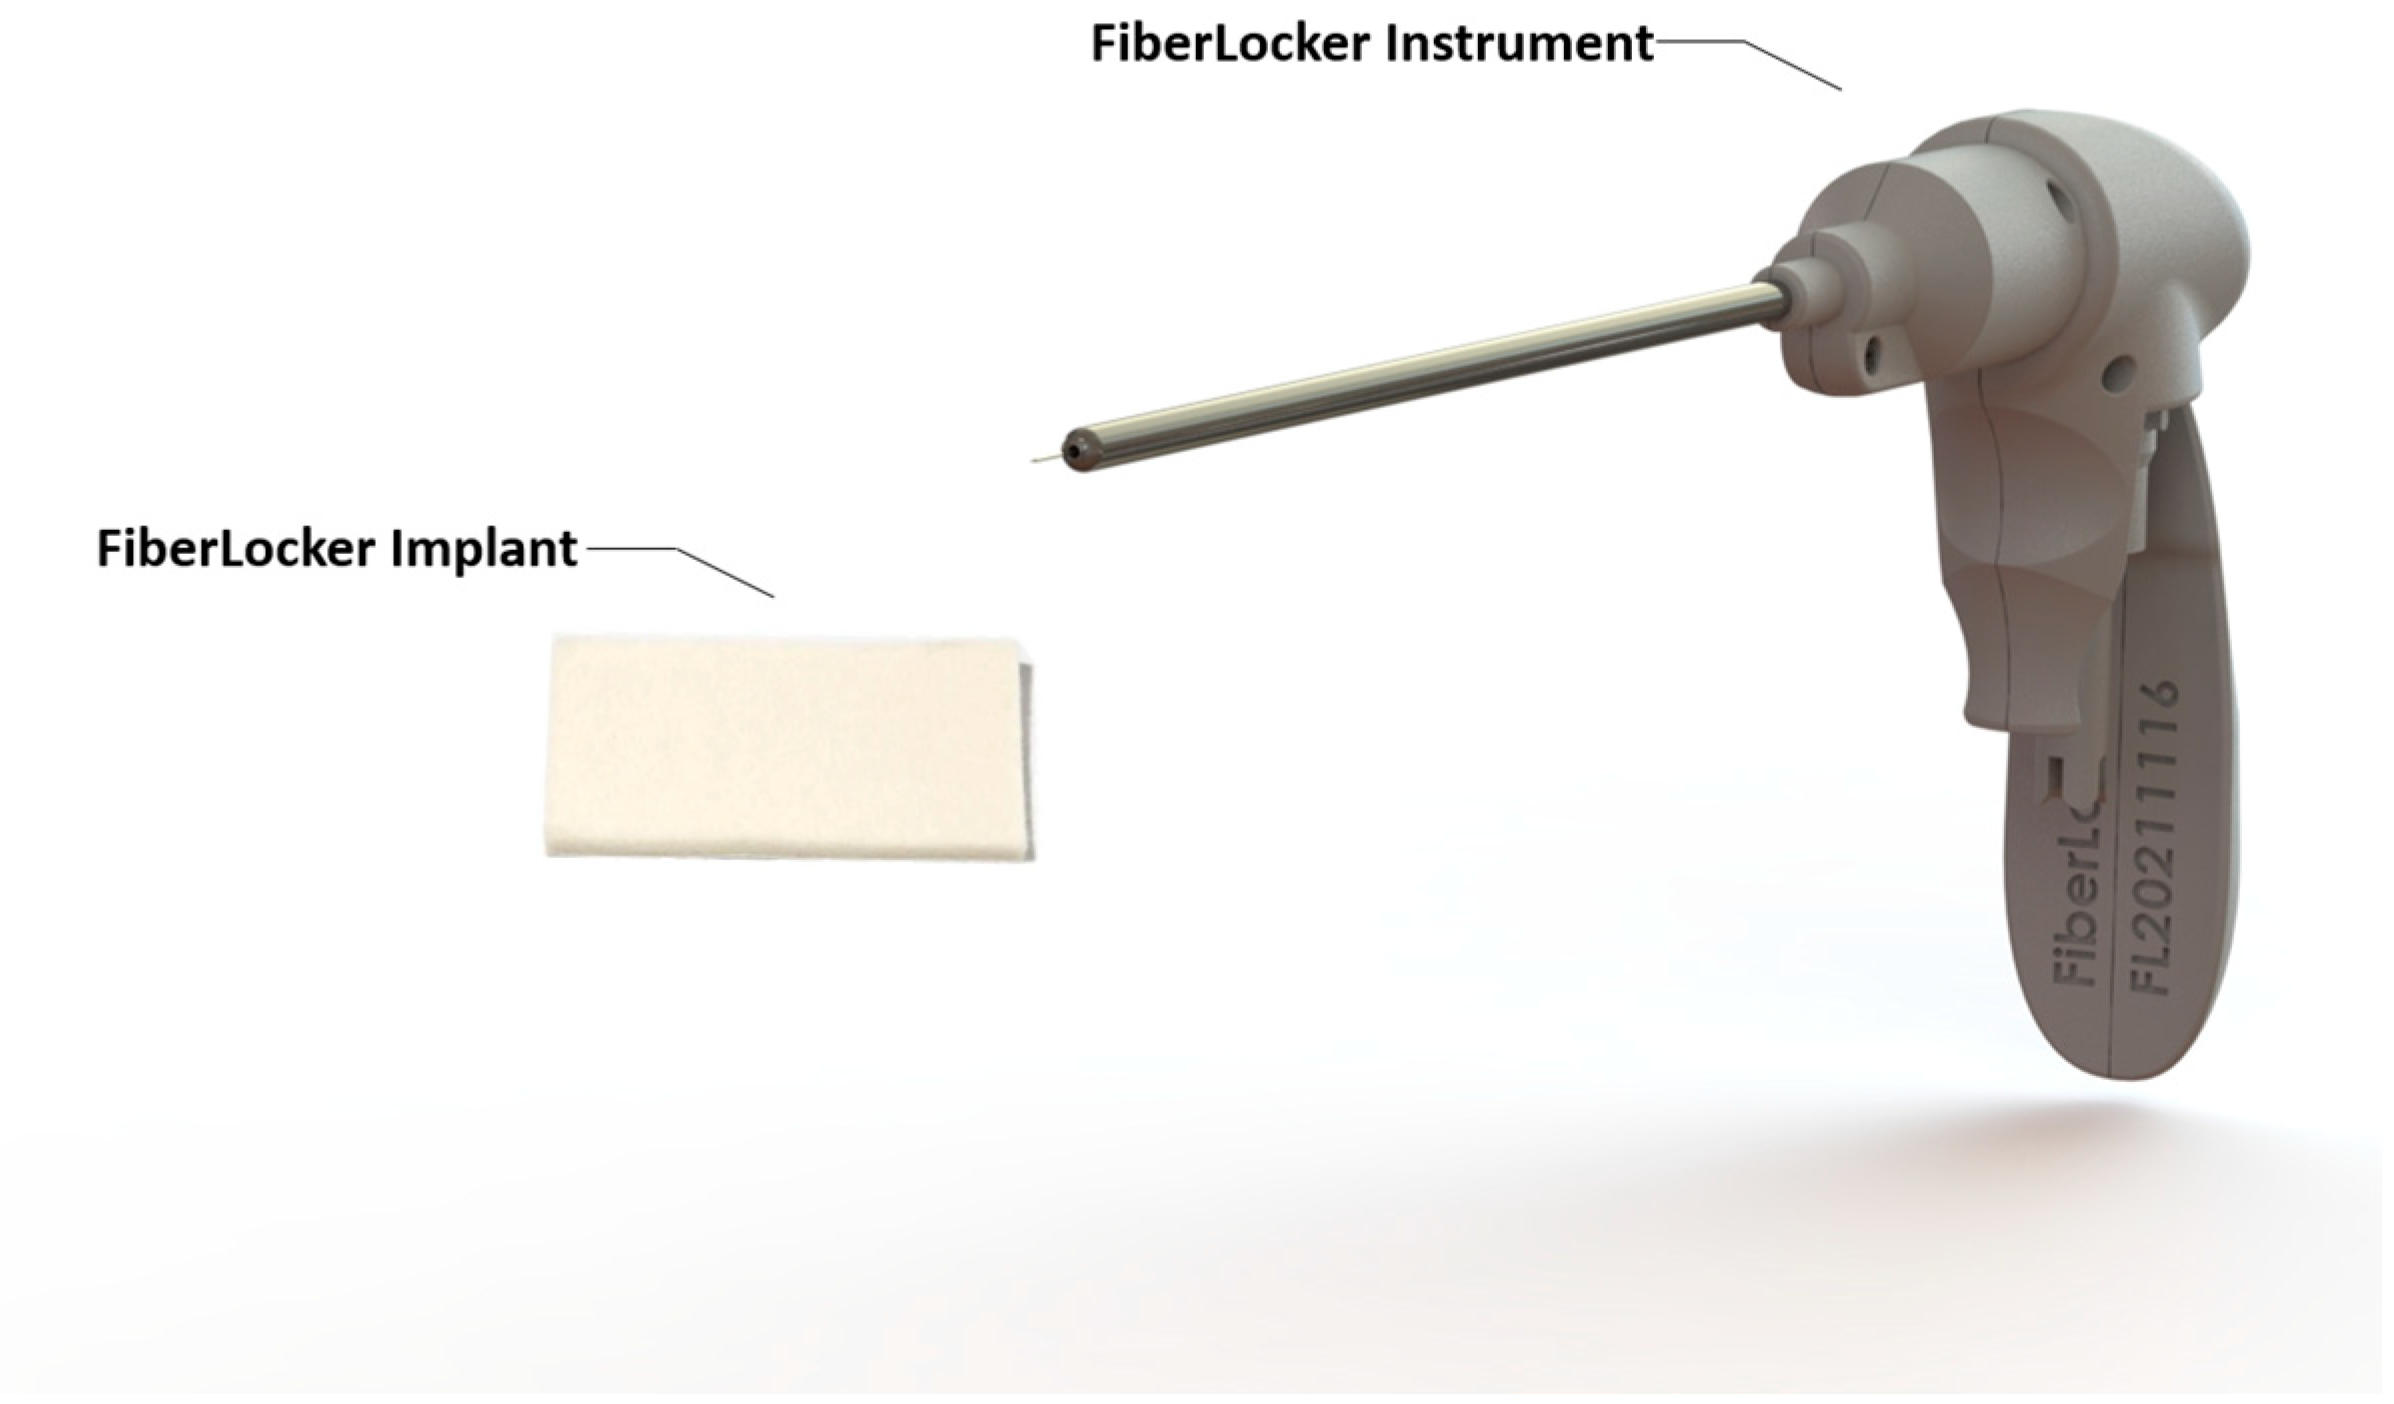

3.1.6. Bioresorbable Scaffolds

3.2. PASTA Lesions